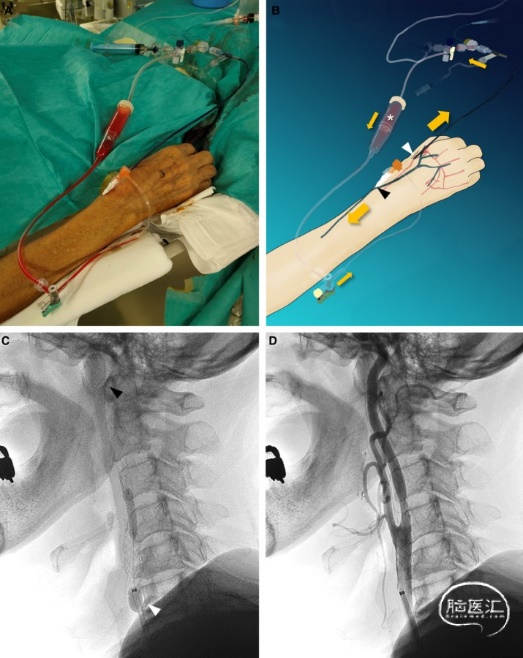

图2. 前臂血流反向回路颈动脉支架置入的说明性病例。A、实际治疗程序。B、逆流系统和血流回路示意图。通过DRA(白色箭头)直接引入球囊引导导管(8 Fr Optimo EPD;Tokai Medical Products,Japan),并将4-Fr 10 cm长的MERIT MAK(MERIT Medical Systems,USA)插入前臂静脉,作为带有Optimo腔室(Tokai;白色星号)的血液回流回路(黑色箭头)。橙色箭头表示前臂血流反向回路系统下的血流。一名左颈颈内动脉狭窄患者接受CASPER RX(Terumo)支架治疗。C、在远端过滤器(Spider FX,美敦力;黑色箭头)和带Optimo充气(白色箭头)的逆流回路的双重保护下,使用SHIDEN(日本Kaneka)进行支架后球囊血管成形术。D、狭窄的颈内动脉扩张良好,证实再通成功。